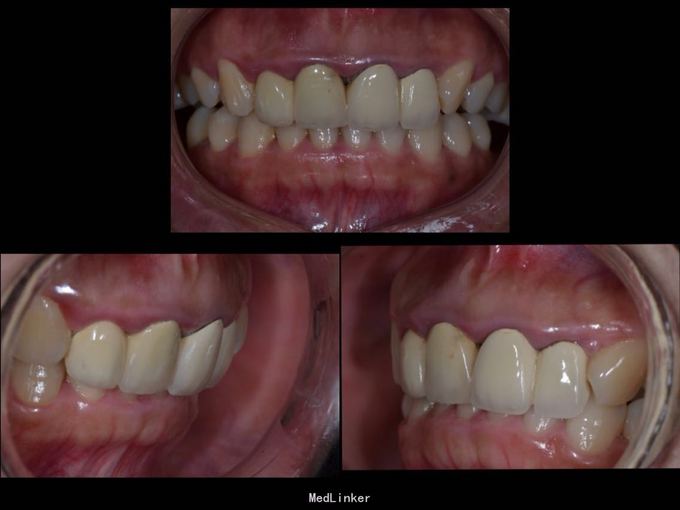

上门牙外伤金属烤瓷冠修复七年,牙龈发黑,红肿,有异味,颜色黄不美观,其他牙也黄不美观,要求重新修复

11 12 21 22金属烤瓷冠修复,牙龈发黑,冠颈部牙龈萎缩红肿有黑褐色腐质物,探出血,叩(-).23近中颊侧扭转倾斜.36 37 46 47残根,松动轻,全口牙结石中度,牙齿颜色偏黄,全景片示,11 12 21 22根管治疗不完善,根尖低密度影,有金属桩修复